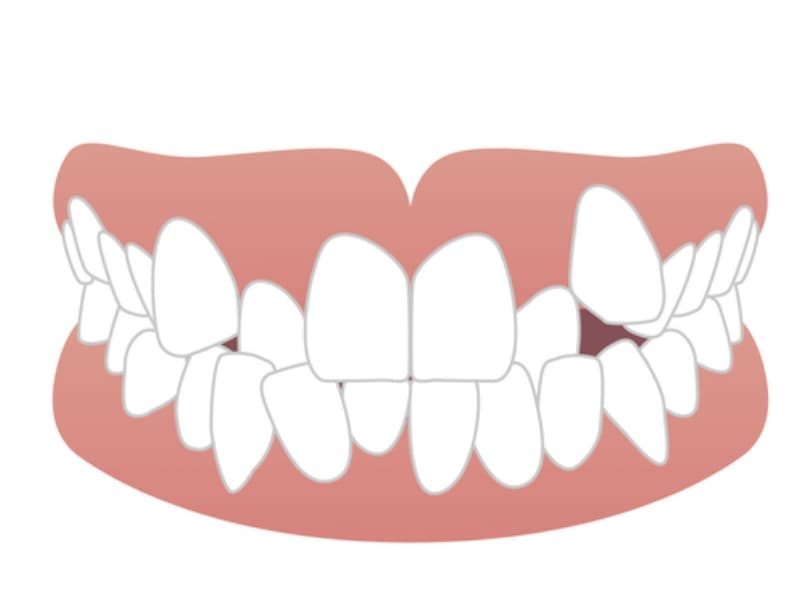

叢生

歯列弓のスペースが不足しているために、歯が重なり合ったり、捻れたりしている状態です。叢生は、歯垢の蓄積を助長し、むし歯や歯周病のリスクを高めます。また、歯ブラシが届きにくい部分ができるため、口腔衛生の維持が難しくなります。

空隙歯列

歯と歯の間に過剰なスペースがある状態を指します。空隙歯列は、発音の明瞭性を損ない、食べかすが溜まりやすくなります。また、隣り合う歯が傾いてくるなどの、二次的な歯列不正を引き起こすこともあります。